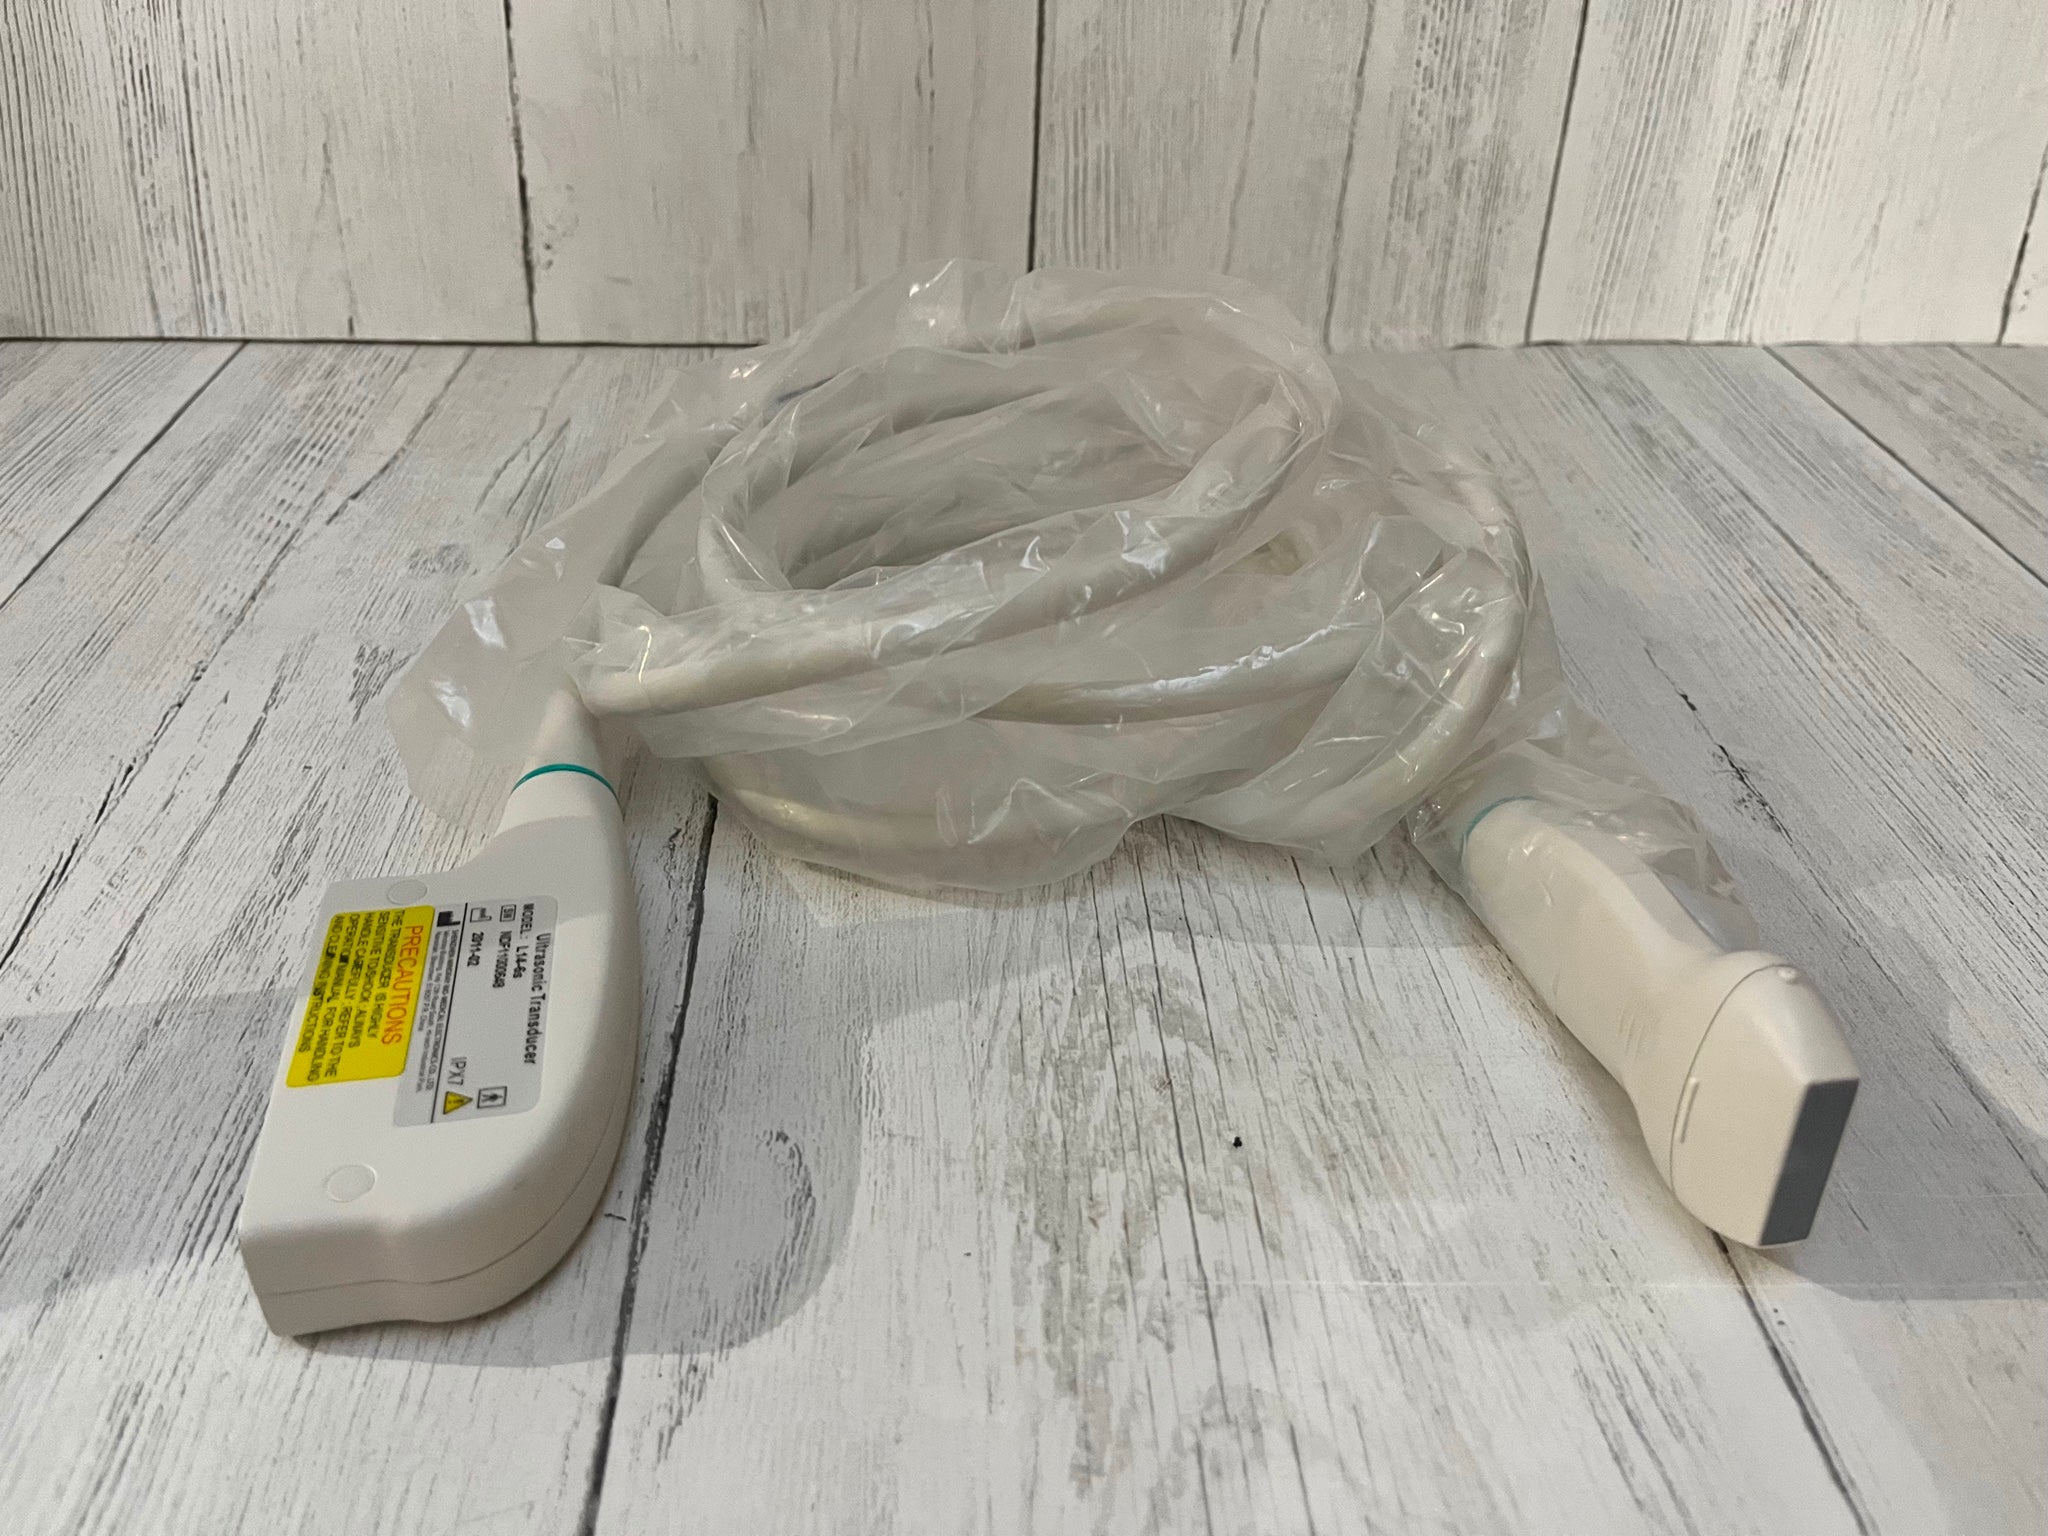

SONOSITE L25X LINEAR FOR M-TURBO EDGE S - Top-Notch Ultrasound Probe

SONOSITE L25X LINEAR FOR M-TURBO EDGE S-NERVE TRANSDUCER - Ultrasound Probe

The SONOSITE L25X LINEAR FOR M-TURBO EDGE S is a premier ultrasound transducer designed to provide high-quality imaging for a variety of clinical applications. This specialized probe is compatible with the SONOSITE M-TURBO EDGE system, a leading point-of-care ultrasound device that delivers exceptional image clarity and reliability. Whether you are in emergency medicine, regional anesthesia, or vascular procedures, the SONOSITE L25X LINEAR provides precise and reliable results every time.

Designed with advanced technology, the SONOSITE L25X LINEAR FOR M-TURBO EDGE S offers a frequency range that is optimal for superficial imaging, aiding healthcare professionals in obtaining detailed and accurate images. The probe's ergonomic design ensures ease of use during extended scanning sessions, reducing operator fatigue. SONOSITE, a brand known for its innovation and quality, ensures that every detail of the L25X LINEAR is tailored to meet the high demands of modern medical environments.

In addition to its superior imaging capabilities, the SONOSITE L25X LINEAR FOR M-TURBO EDGE S is built to withstand the rigors of everyday clinical use. Its durable construction means it can handle frequent cleaning and disinfection processes essential in maintaining hygiene standards in medical settings. Investing in this ultrasound probe not only enhances diagnostic accuracy but also ensures a reliable performance that stands the test of time.

The SONOSITE L25X LINEAR FOR M-TURBO EDGE S is also known for its quick-and-easy setup, which saves valuable time in fast-paced clinical settings. Furthermore, it offers seamless integration with the SONOSITE M-TURBO EDGE system, providing a user-friendly experience that complements the workflow of healthcare professionals. This leads to improved patient care and optimized clinical operations.

For any healthcare facility looking to enhance its ultrasound imaging capabilities, the SONOSITE L25X LINEAR FOR M-TURBO EDGE S is a worthy investment. Its high-resolution imaging, durability, and user-oriented design make it a standout choice in the market. With the SONOSITE L25X LINEAR, clinicians can perform accurate diagnoses, carry out intricate procedures with confidence, and ultimately, improve patient outcomes. Don't miss out on the opportunity to advance your practice with this exceptional ultrasound probe.